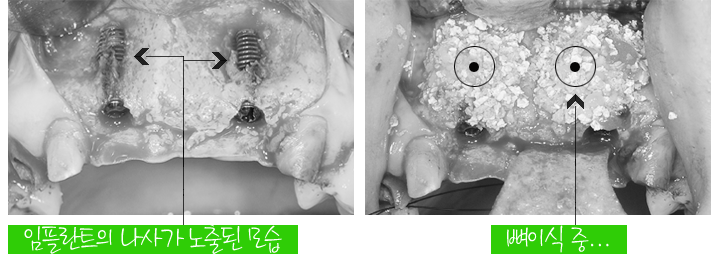

브릿지를 제거했습니다

치아에 충치와 염증이 진행되고 있습니다

치료는 빠진 치아는 임플란트 2개 식립후 3개의 치아를 결합하기로 계획했고

나머지 치아는 크라운 재치료를 계획했습니다

앞니에 임플란트 2개를 식립했는데

사진을 보시면 잇몸뼈가 부족해서 임플란트의 나사가 노출된 모습입니다

임플란트는 잇몸뼈와 단단히 굳어야하는데

사진과 같이 임플란트가 노출되면 성공적인 임플란트 치료를 기대하기 어렵기 때문에

뼈이식을 통해서 부족한 잇몸뼈를 보충해줘야합니다

임플란트 식립과 잇몸뼈이식을 진행했습니다